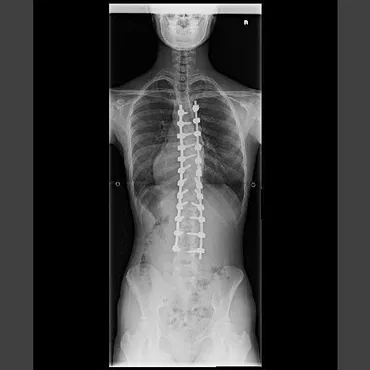

✅ 側弯症は脊柱が横に曲がり、ねじれを伴う疾患で、多くは原因不明の特発性側弯症で学童期や思春期に発症。コブ角10度以上で側弯と診断され、進行度合いによって治療法が選択される。

✅ 治療法は、軽度(コブ角25度未満)の場合は経過観察、進行性のある場合は装具療法、高度な弯曲(胸椎45~50度以上、腰椎40度以上)の場合は手術が検討される。

✅ 手術治療では、より安全で侵襲の少ない矯正固定術として、椎弓根スクリューとロッドを用いた固定術が行われ、手術時間短縮や出血量減少のため、一部の椎骨をスキップする術式(Skip Pedicle Screw Fixation)が考案されている。

脊柱側弯症は、脊柱が側方に曲がる病気で、椎骨のねじれを伴うこともあります。

コブ角によって重症度が評価され、10度以上で側弯症と診断されます。

手術には、背中から行う「後方矯正固定術」と、胸部または腹部から行う「前方矯正固定術」があります。

当センターでは、前方矯正固定術を小切開で行う手術システムを開発しており、特に若い女性の特発性側彎症の治療に適しています。